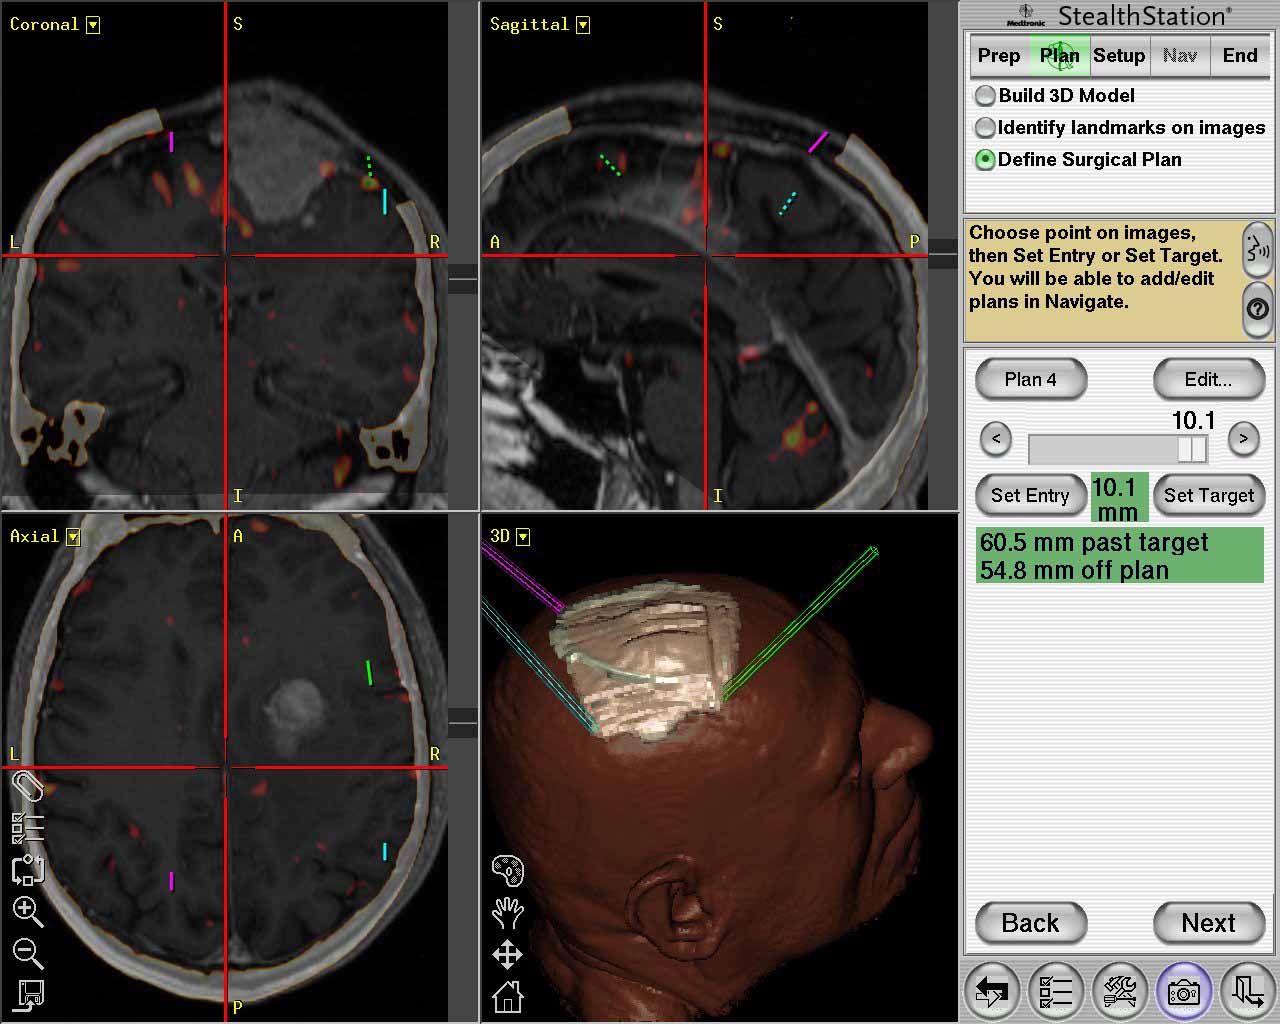

Tecnica

terapeutica non invasiva

che utilizza radiazioni ad

alta precisione per trattare lesioni del cervello e del

sistema nervoso, senza

incisioni chirurgiche, preservando i tessuti sani

circostanti. |

| Meningioma

con demolizione-ricostruzione della teca cranica in un unico tempo

con tecnica microchirurgica e neuronavigazione. |